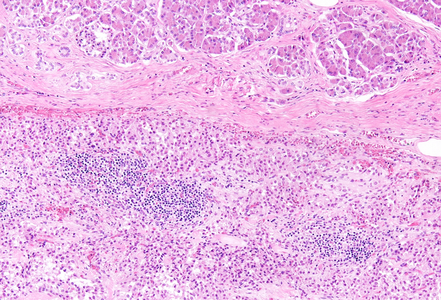

A distal (caudal) pancreatectomy was performed on a 52-year-old female who presented with a macroscopically cystic pancreatic tumor containing firm and solid areas, measuring 6 cm in greatest dimension.

Histological examination revealed a well-circumscribed neoplasm with a fibrous capsule (Panel A), composed of uniform, poorly cohesive cells arranged in both solid (Panel B) and pseudopapillary structures (Panel C). The pseudopapillae resulted from degenerative changes leading to detachment of tumor cells from another and from central fibrovascular cores. Stromal hyalinization was also noted (Panel D). The neoplastic cells were monomorphic, with round to oval nuclei showing finely dispersed chromatin, inconspicuous nucleoli, and moderate amounts of eosinophilic to clear cytoplasm. Mitoses were not seen.